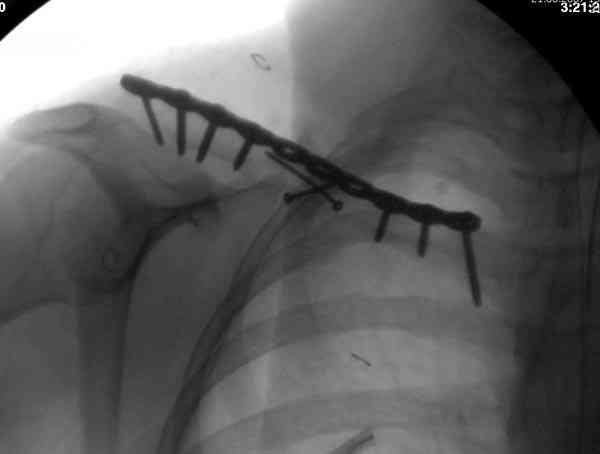

Недавно разбирали случай ложного сустава.

45 летная женщина после автоаварии, алкоголь 163 и 20 летним стажем курения.

Консервативное лечение, через 8 мес. операция Rockwood pin с костной пластикой в нашем городе другим врачом. После 8 недели падение, гвоздь удален оперирующим хирургом, больная направлена к нам. Фиксация реконструктивной пластиной с трикортикальным графтом, добавлен BMP-2. Для стабилизации фиксацию провели через акромион.

Вот уже два месяца больная также продолжает жаловаться на боли, буквально на днях удалили акромиальную часть пластины с специальной пилой с алмазным покрытием для медицинского металла. До сих пор судьба ложного сустава неизвестна....

Второй случай тоже недавно оперирован по поводу

ложного сустава, в марте травма, через 4.5 половиной

операция..